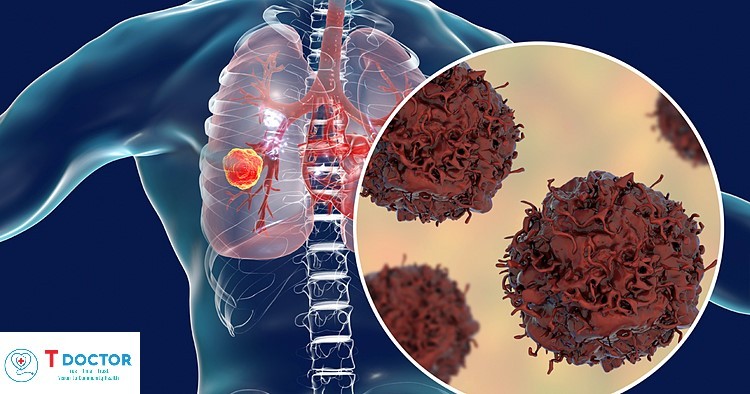

TƯ VẤN CÁC BỆNH UNG THƯ

Bác sĩ, Tiến sĩ LÊ THANH DŨNG

Chuyên khoa ung thư

Bệnh viện Hữu Nghị Việt Đức